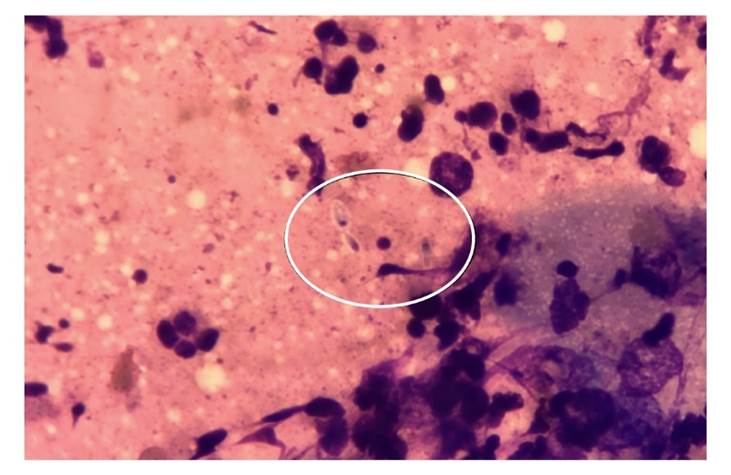

La figura 1 muestra lesiones de diferentes formas clínicas. En más del 85 % de los casos, la punción o biopsia del nódulo subcutáneo fue la muestra que permitió el diagnóstico (cuadro 3). Todos los pacientes fueron diagnosticados por medio del cultivo positivo, mientras que el rendimiento del examen directo fue del 19,2 %.En la figura 2 se muestra la coloración de Giemsa de la muestra clínica obtenida por escarificación de la lesión cutánea de la pierna del paciente de la figura 1A. La imagen del microcultivo de Sporothrix spp. se presenta en la figura 3.

Figura 3 Microcultivo a 28 °C de Sporothrix spp., obtenido en cultivo primario. Azul de lactofenol, 400X.